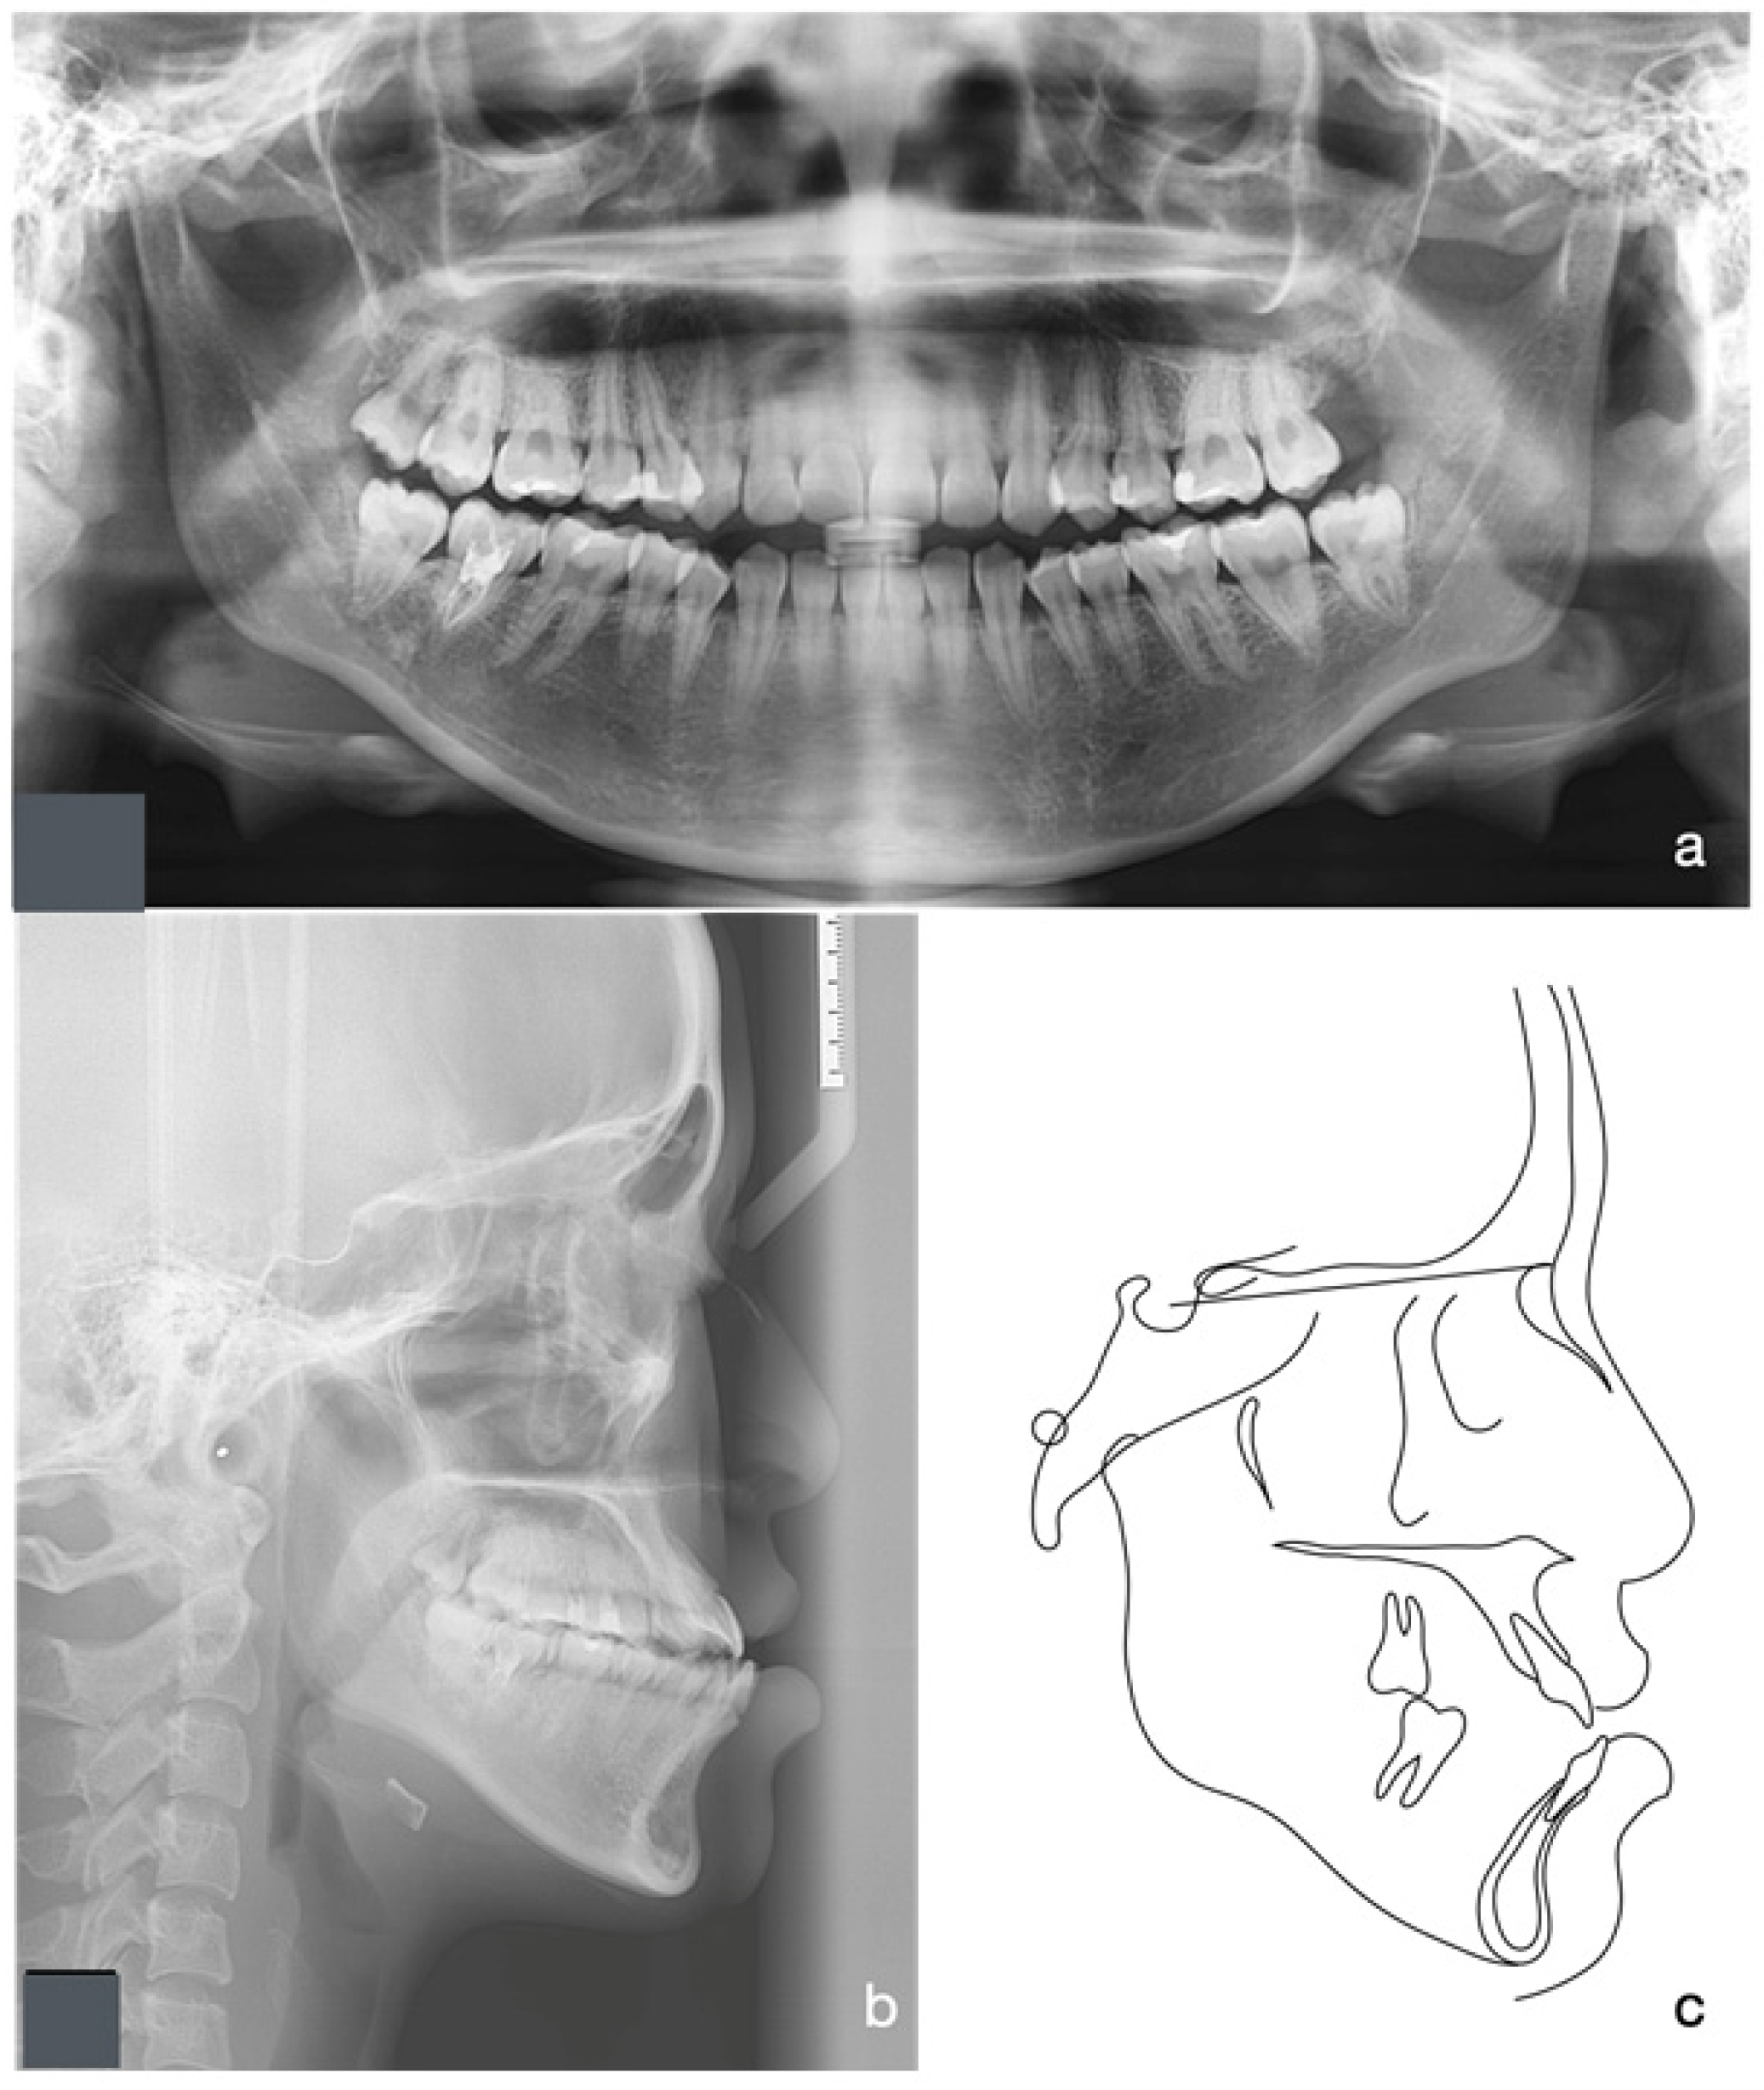

2.5. Treatment Results